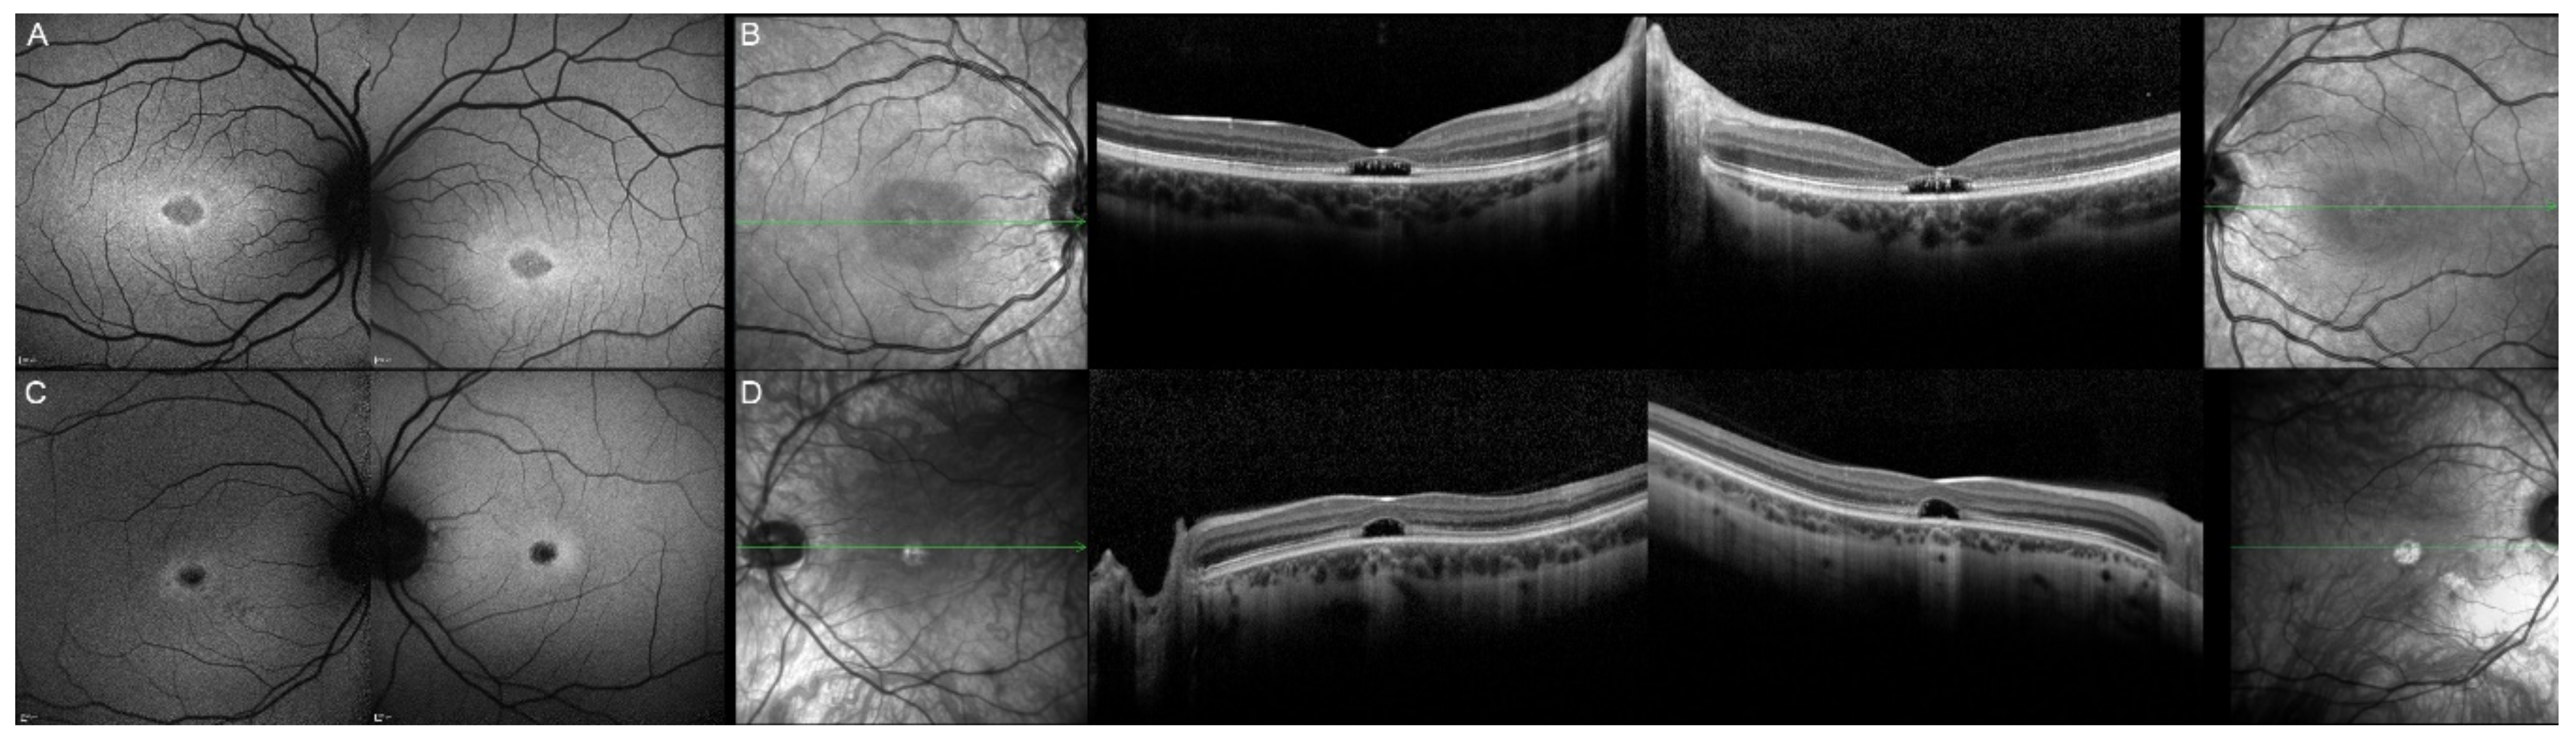

| Patient | Gene | Age | Sex | FAF | OCT |

|---|---|---|---|---|---|

| 17, II.1 | PRPH2 | 51 | F | Butterfly pattern of HPAF and HOAF flecks; paramacular to mid-peripheral HPAF flecks | Irregular EZ thickening |

| 18, II.2 | PRPH2 | 69 | M | Subfoveal HOAF (OS); butterfly pattern of HPAF and HOAF flecks; paramacular to mid-peripheral HPAF flecks | Central EZ loss (OS); central ONL atrophy (OS); localised ONL thinning (OD) |

| 19, III.2 | PRPH2 | 39 | F | Central areolar HOAF; disseminated nummular HPAF | Extended retinal atrophy |